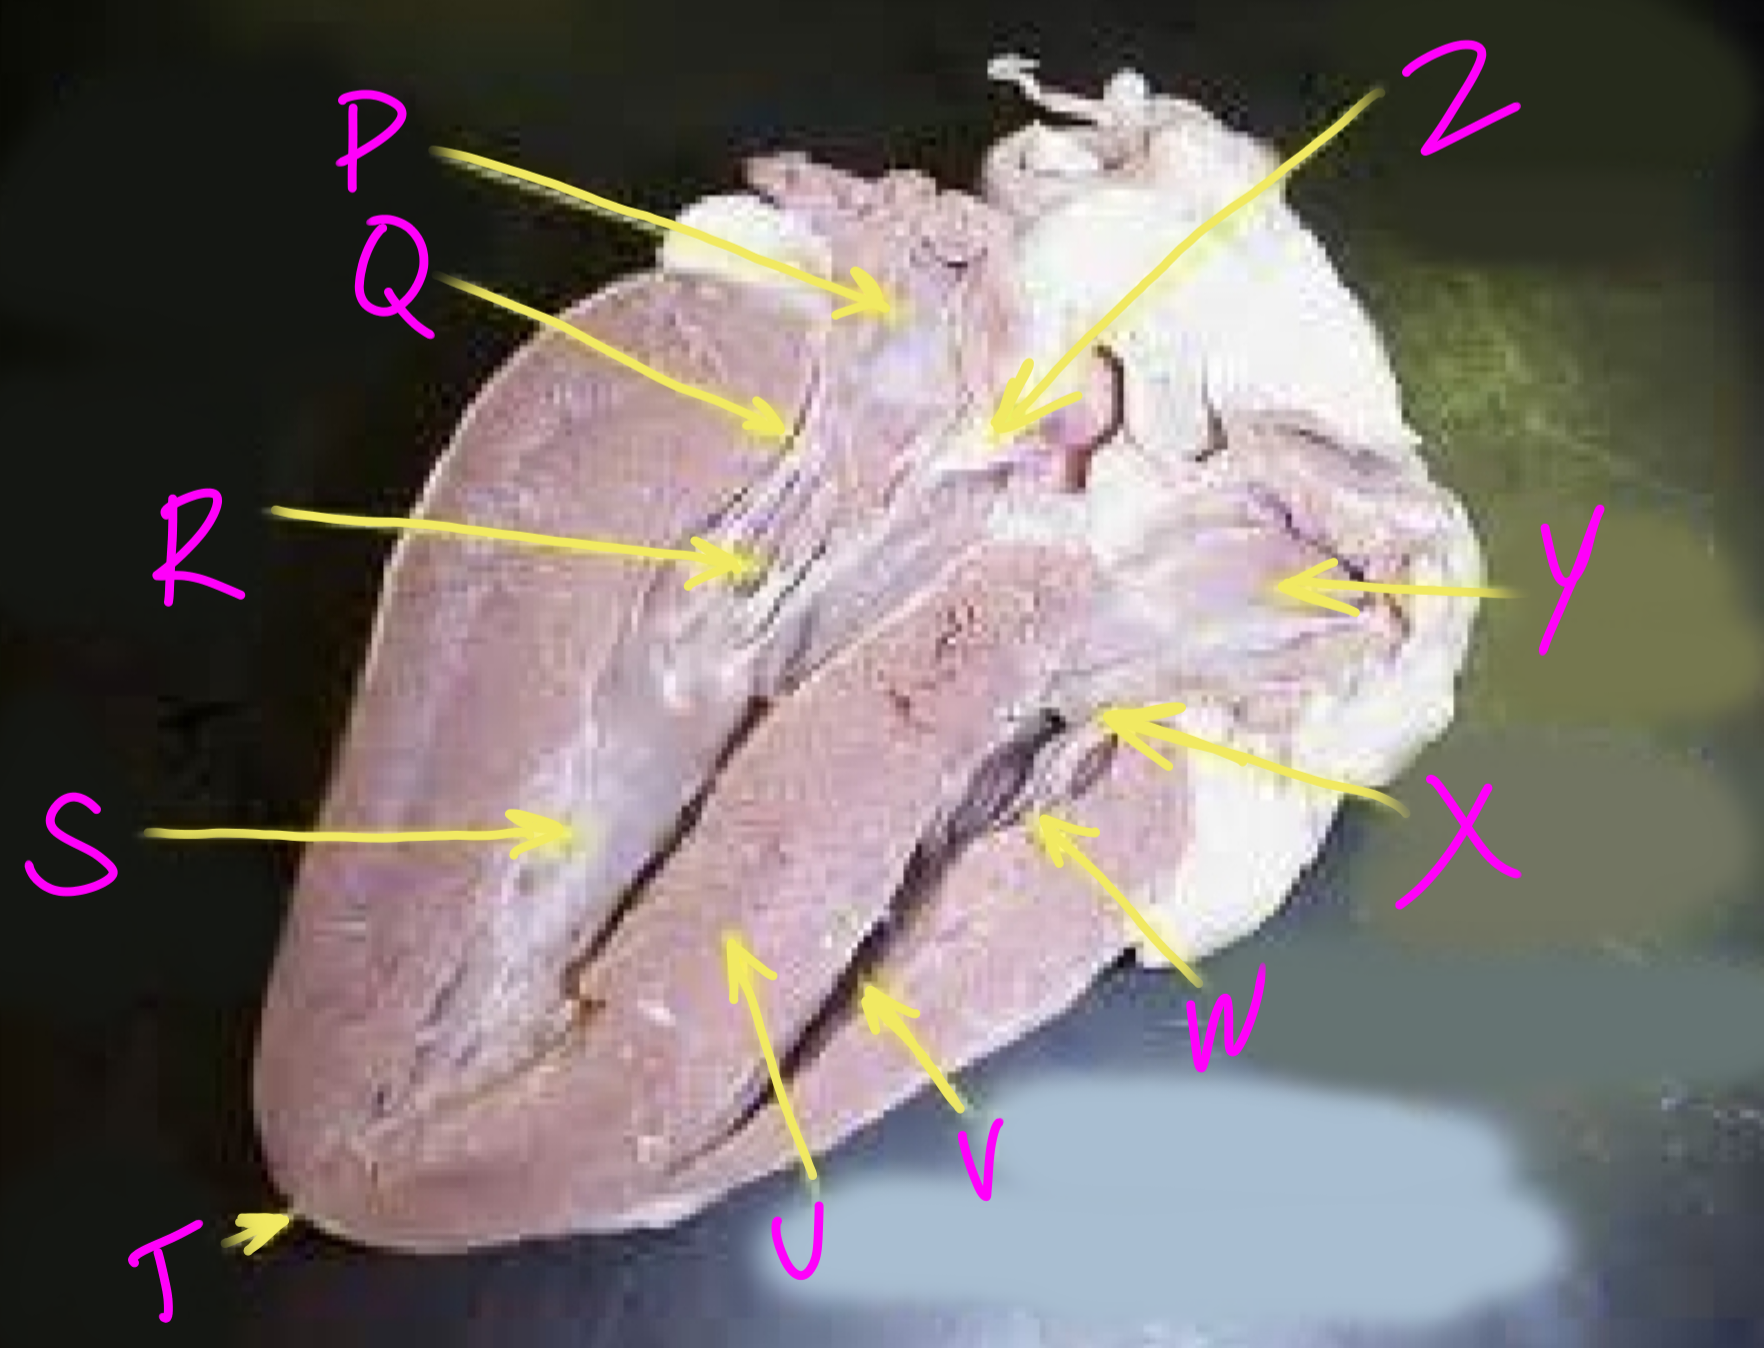

P

Left atrium

Q

Bicuspid valve - allows blood to flow from the left ventricle to the aorta

R

Right chordae tendinae - hold AV valves in place

S

Left ventricle

T

Apex - pumps blood out of the ventricles

U

Interventricular septum - divides the right and left ventricles

V

Right ventricle

W

Left chordae tendinae - hold AV valves in place

X

Tricuspid valve

Y

Right atrium

Z

Aortic semilunar valve - prevent backflow